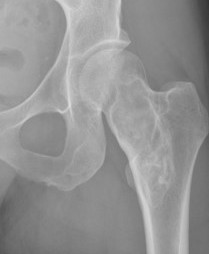

X-ray

Intramedullary lucent diaphyseal lesion with 'ground glass appearance'

- thinned, slightly bulged cortex

- ± endosteal scalloping

- may have angular deformity / bowing

Coxa vara and Shepherd's Crook deformity of proximal femur

- Shepherd's Crook - anterior bowing of femur

- secondary leg length discrepancy

- pain, difficulty walking